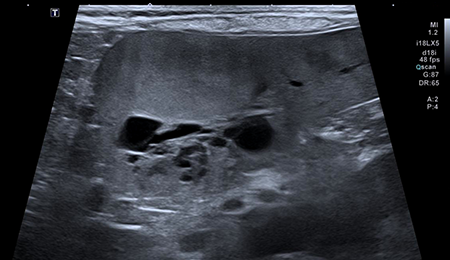

초음파 진단 케이스

간 종양

담낭점액종

소장 이물

비장 종괴

다낭성 신장

방광종괴

이첨판폐쇄부전(MMVD)

심비대증 (HCM)

심장기형(PDA)